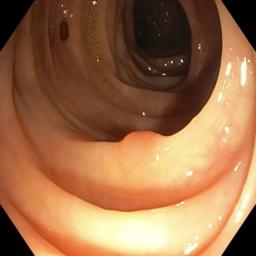

Polyp segmentation in medical imaging is crucial for the early detection and treatment of colorectal cancer [1, 2, 3, 4, 5, 6]. Accurate identification and delineation of polyps can significantly impact patient outcomes, but the task remains challenging due to variations in imaging conditions, equipment, and patient demographics. Traditional machine learning approaches for polyp segmentation often face difficulties when applied to data from different sources or domains, leading to reduced performance and generalization issues. Another difficulty is more common: constructing a large, diverse dataset is essential for robust and successful models, yet gathering such data in a centralized manner is often infeasible due to privacy laws and ethical concerns.

In this paper, we propose a novel approach that combines federated learning with frequency-based domain generalization techniques to enhance polyp segmentation. By incorporating frequency domain analysis, we aim to capture and leverage important features that contribute to improved domain generalization. Our approach addresses both the privacy concerns and the domain variability issues, leading to more accurate and robust polyp segmentation models. This innovative method, to our knowledge, is the first to combine these techniques, making it not only a powerful solution for polyp segmentation but also has a high potential to apply to a wide range of medical segmentation tasks such as retina fundus [13], pancreas [14], breast [15], liver [16, 17], brain [18], and others [19] due to its generic nature.